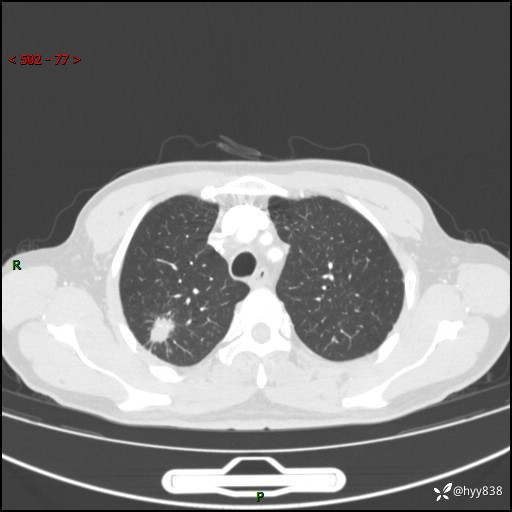

69岁/男,发现肺部病变6天。该有的征象都有,肉芽肿 VS 肿瘤,一念之间---(有结果)

主诉:发现肺部病变6天。

现病史:患者6天前于我院泌尿外科住院,住院期间行胸部CT检查,提示“肺部病变”,患者无畏寒、发热、盗汗、咳嗽、咳痰、咯血、胸痛、呼吸困难,无反酸、腹痛、腹泻、头痛、头晕等不适。未予特殊处理,现为进一步诊治,门诊以“肺肿物”收入我科。 患者本次起病以来,精神食欲尚可,大小便正常,体力及体重无明显变化。

胸部CT平扫+增强